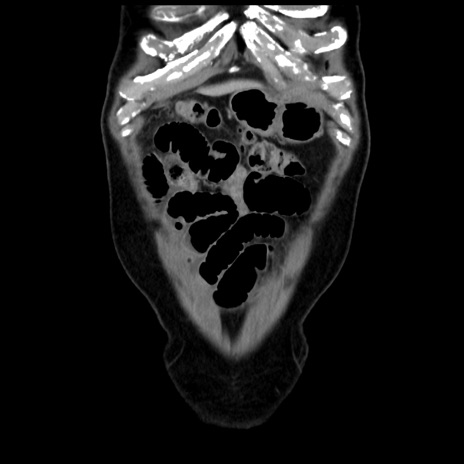

横断像

症例16(冠状断像)

【症例】 70歳代男性

【主訴】 腹痛、嘔吐

【現病歴】 約1ヶ月前より間欠的に腹痛と嘔吐あり、当院消化器内科を受診したところCTで多発する肝臓のLDAを指摘され、精査中であった。以降は消化器症状は安定していたが、2日前より嘔気と腹痛があり、同日より排便・排ガスが消失した。改善認めず、 本日、救急外来を受診した。